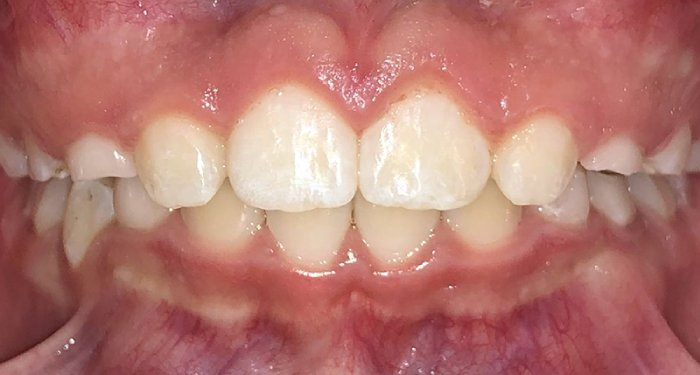

Actual Patient: Addilyn

invisalign kids actual patient after invisalign kids actual patient before

Severe Crowing, Narrow Jaws, Open Bite, Mouth Breather

invisalign kids actual patient after 1 invisalign kids actual patient before 1

Front View

Top View

Right & Left Sides